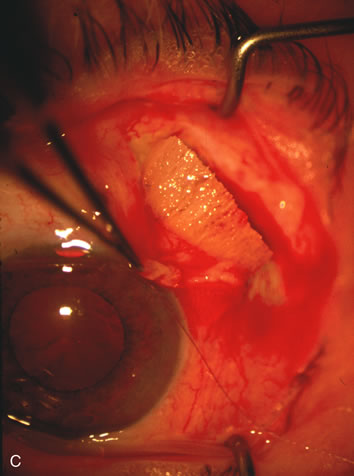

The inflammation associated with lens extraction at any site usually causes complete failure of a marginal functioning bleb. In addition, pressure reduction by medical means is usually minimal in these recalcitrant cases, and combined surgery is indicated. In the past, these cases were approached with large-incision ECCE, clear corneal cataract incision, and bleb revision. Drawbacks included those mentioned earlier for large incision clear corneal cataract extraction, and bleb revision is often associated with conjunctival buttonholes, wound leaks, subconjunctival hematoma, destruction of friable sclera, and associated hypotony. With the advent of modern-day cataract surgery, a phacotrabeculectomy is often possible adjacent to the failed filter (Fig. 7). The ability to combine cataract extraction with implant and filtration surgery all through the same small incision has greatly improved outcomes for patients with marginal preoperative filters. There are several other viable options in this case. If the surgeon elects to remove the cataract through a temporal clear corneal incision, the bleb may be revised or a new adjacent filter fashioned. As mentioned earlier, revising a failed filter is technically challenging. If the surgeon believes it is not feasible to revise the filter or fashion a new one, a glaucoma drainage implant is a reasonable option combined with temporal lens extraction.172

Fig. 7. Phacotrabeculectomy adjacent to a failed filter in cataractous eye. The ability to combine small-incision cataract extraction with trabeculectomy all through the same incision adjacent to the failed filter allows the surgeon to work in a familiar superior area. Avoiding incisions into the existing bleb decreases conjunctival buttonholes, hypotony, operating room time, and subconjunctival bleeding. A. Appearance of failed bleb with exposure of superior temporal quadrant gained with a corneal traction suture. B. Prepare a limbus-based conjunctival flap and a scleral flap. C. This bleb is at high risk to fail again justifying the need for MMC, 0.2 mg/cc applied on a pledget for 4 minutes. D. Insert the keratome and perform phacotrabeculectomy in the usual fashion.